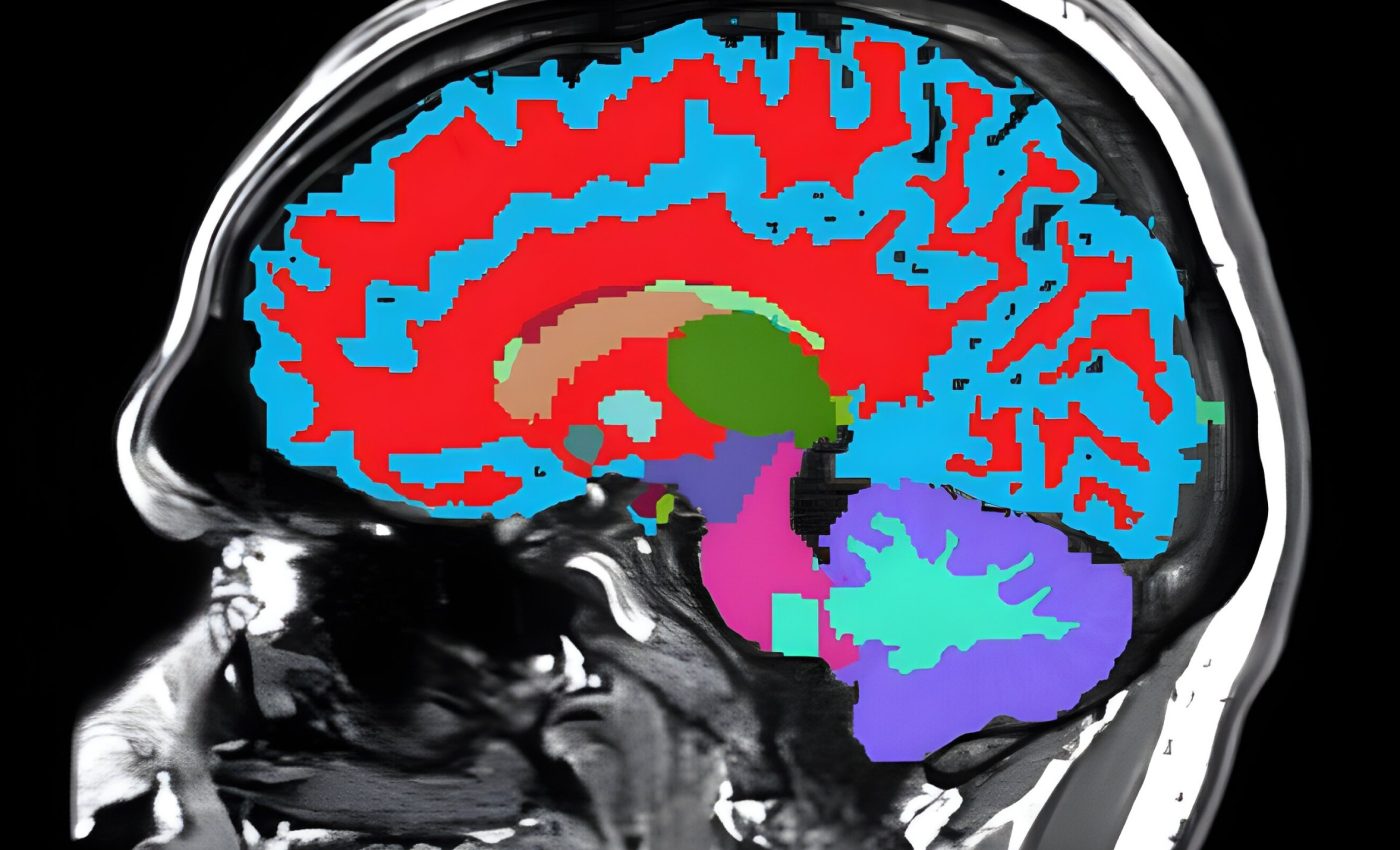

Scientists from Duke University, Harvard University, and the University of Otago in New Zealand have created a tool that uses a single brain scan to estimate how quickly your body and mind are aging. And it does this while you’re still in midlife, before major health problems show up.

The new tool, called DunedinPACE Neuroimaging or DunedinPACNI, can be used with a standard MRI brain scan. It gives doctors and researchers a read on your aging pace and potential risk for chronic diseases long before symptoms appear.

The team trained DunedinPACNI to predict that rate of aging based only on brain scans taken when the participants were 45. Once the model was trained, it was tested on other datasets from the U.S., U.K., Canada, and Latin America.

Image Credit: Ethan Whitman, Duke University